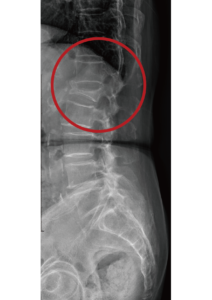

針對壓迫性骨折,X光的檢查是最基本的,尤其是一系列的X光記錄(比如每星期照一次做比對),可以發現脊椎的椎體變成楔狀(Wedge shape),也就是椎體的高度減少了,時間久一點甚至椎體裡還會出現空氣,就是告訴我們骨折沒有癒合,而且仍然處在不穩定的狀態。雖然X光可以診斷大多數的壓迫性骨折,但有些情況下,比如有很多節的壓迫性骨折,或病人疼痛已經持續一段時間,甚至是還有下肢麻痛的症狀,這些情況是需要利用核磁共振MRI來做進一步的檢查。

手術前               手術後

目前手術治療是以椎體成形術(Vertebroplasty)為主流,椎體成形術是在手術室裡利用X光機的導引,將椎體穿刺針插入椎體中,灌入骨水泥來支撐已經塌陷的椎體,有時還會利用水球或是俗稱千斤頂的椎體支架,來獲得更好的支撐效果。手術時間大概需要20分鐘,傷口小、安全、疼痛少、恢復迅速,是現在主要的治療方式。